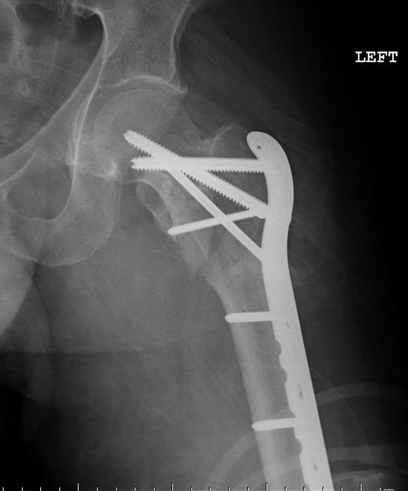

Применили проксимальную Synthes Locking plate, из-за множественных фрагментов посчитали более приемлемым в этом случае (клиника университетская, резиденты должны имет возможность созерцать разные варианты остеосинтеза).

Также старался минимизировать доступ на уровне перелома с субвастус доступом, диафиз фиксирован перкутанно, не стали гонятся за малым вертелом, как смог зафиксировал.